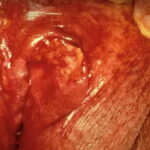

Eosinophilic granuloma =ورم حبيبي بالحمضات